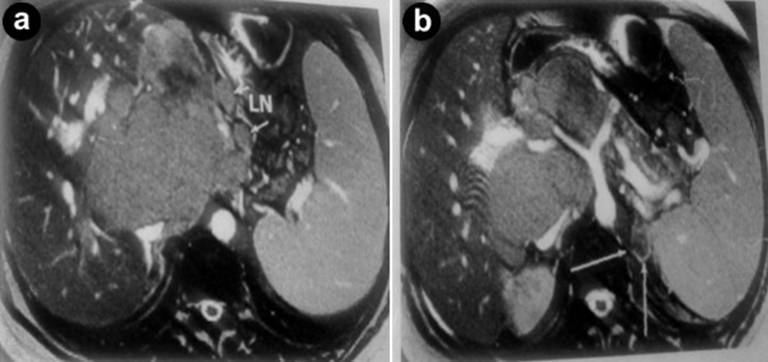

Abdominal MRI (Figure 3) and MRCP (Figure 4) for patient were done. The intra-hepatic bile ducts, main hepatic ducts, CHD and CBD are mildly dilated and displaced to the right side by a large lobulated mass (160×112×130 mm) of pancreatic head with low signal intensity on T1W images and high intensity on T2W images.

Figure 3. The intra-hepatic bile ducts, main hepatic ducts, CHD, CBD are mildly dilated and displaced to the right side by pancreatic head mass (160×112×130 mm) on T1W and T2W images. |

Figure 4. MRCP has shown pancreatic head mass (160×112×130 mm) and mildly dilatation of intra-hepatic bile ducts, main hepatic ducts, CHD and CBD. Region surrounded by multiple lymph nodes (up to 20 mm). |

Region with multiple surrounding lymph nodes (up to 20 mm) compressing portal hepatic and encasing celiac trunk branches without stenosis. The pancreatic duct is only mildly dilated. The spleen has enlarged (170 mm). According low signal intensity on T1W images a 19 mm left adrenal mass detected; it could be an adrenal adenoma.